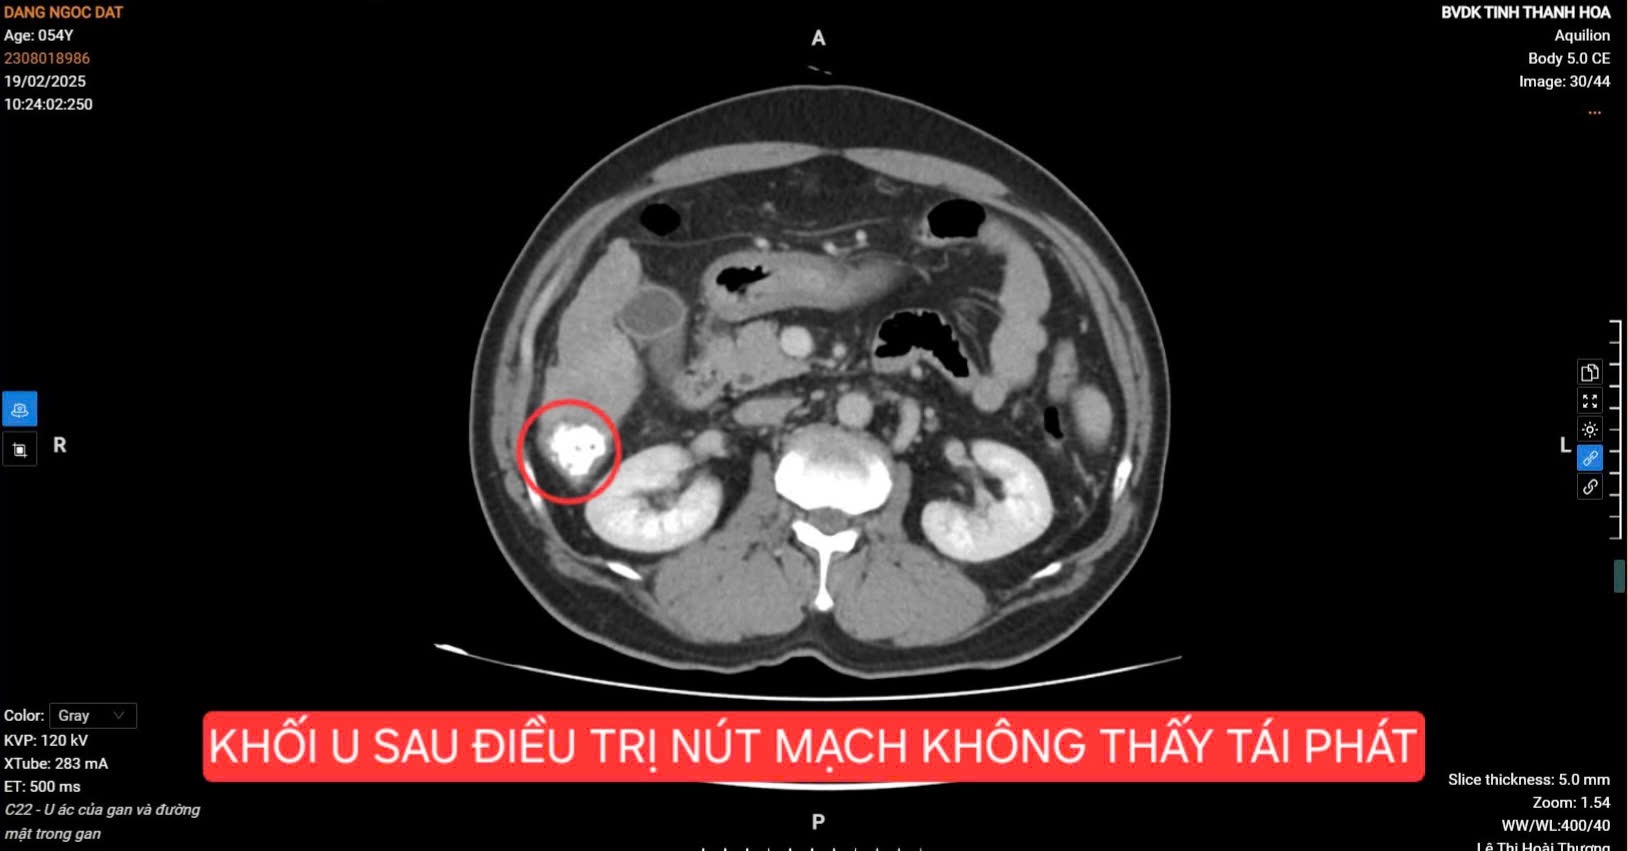

Hình ảnh khối u gan của bệnh nhân sau can thiệp nút mạch

Sau can thiệp nút mạch, bệnh nhân được theo dõi sát sao. Và điều bất ngờ là chỉ sau một lần điều trị nút mạch, sau 9 tháng theo dõi, bệnh nhân tái khám với kết quả: Khối u không còn dấu hiệu tái phát, chỉ số marker ung thư gan (AFP) giảm thấp đáng kể, chỉ còn 8,25 ng/mL.